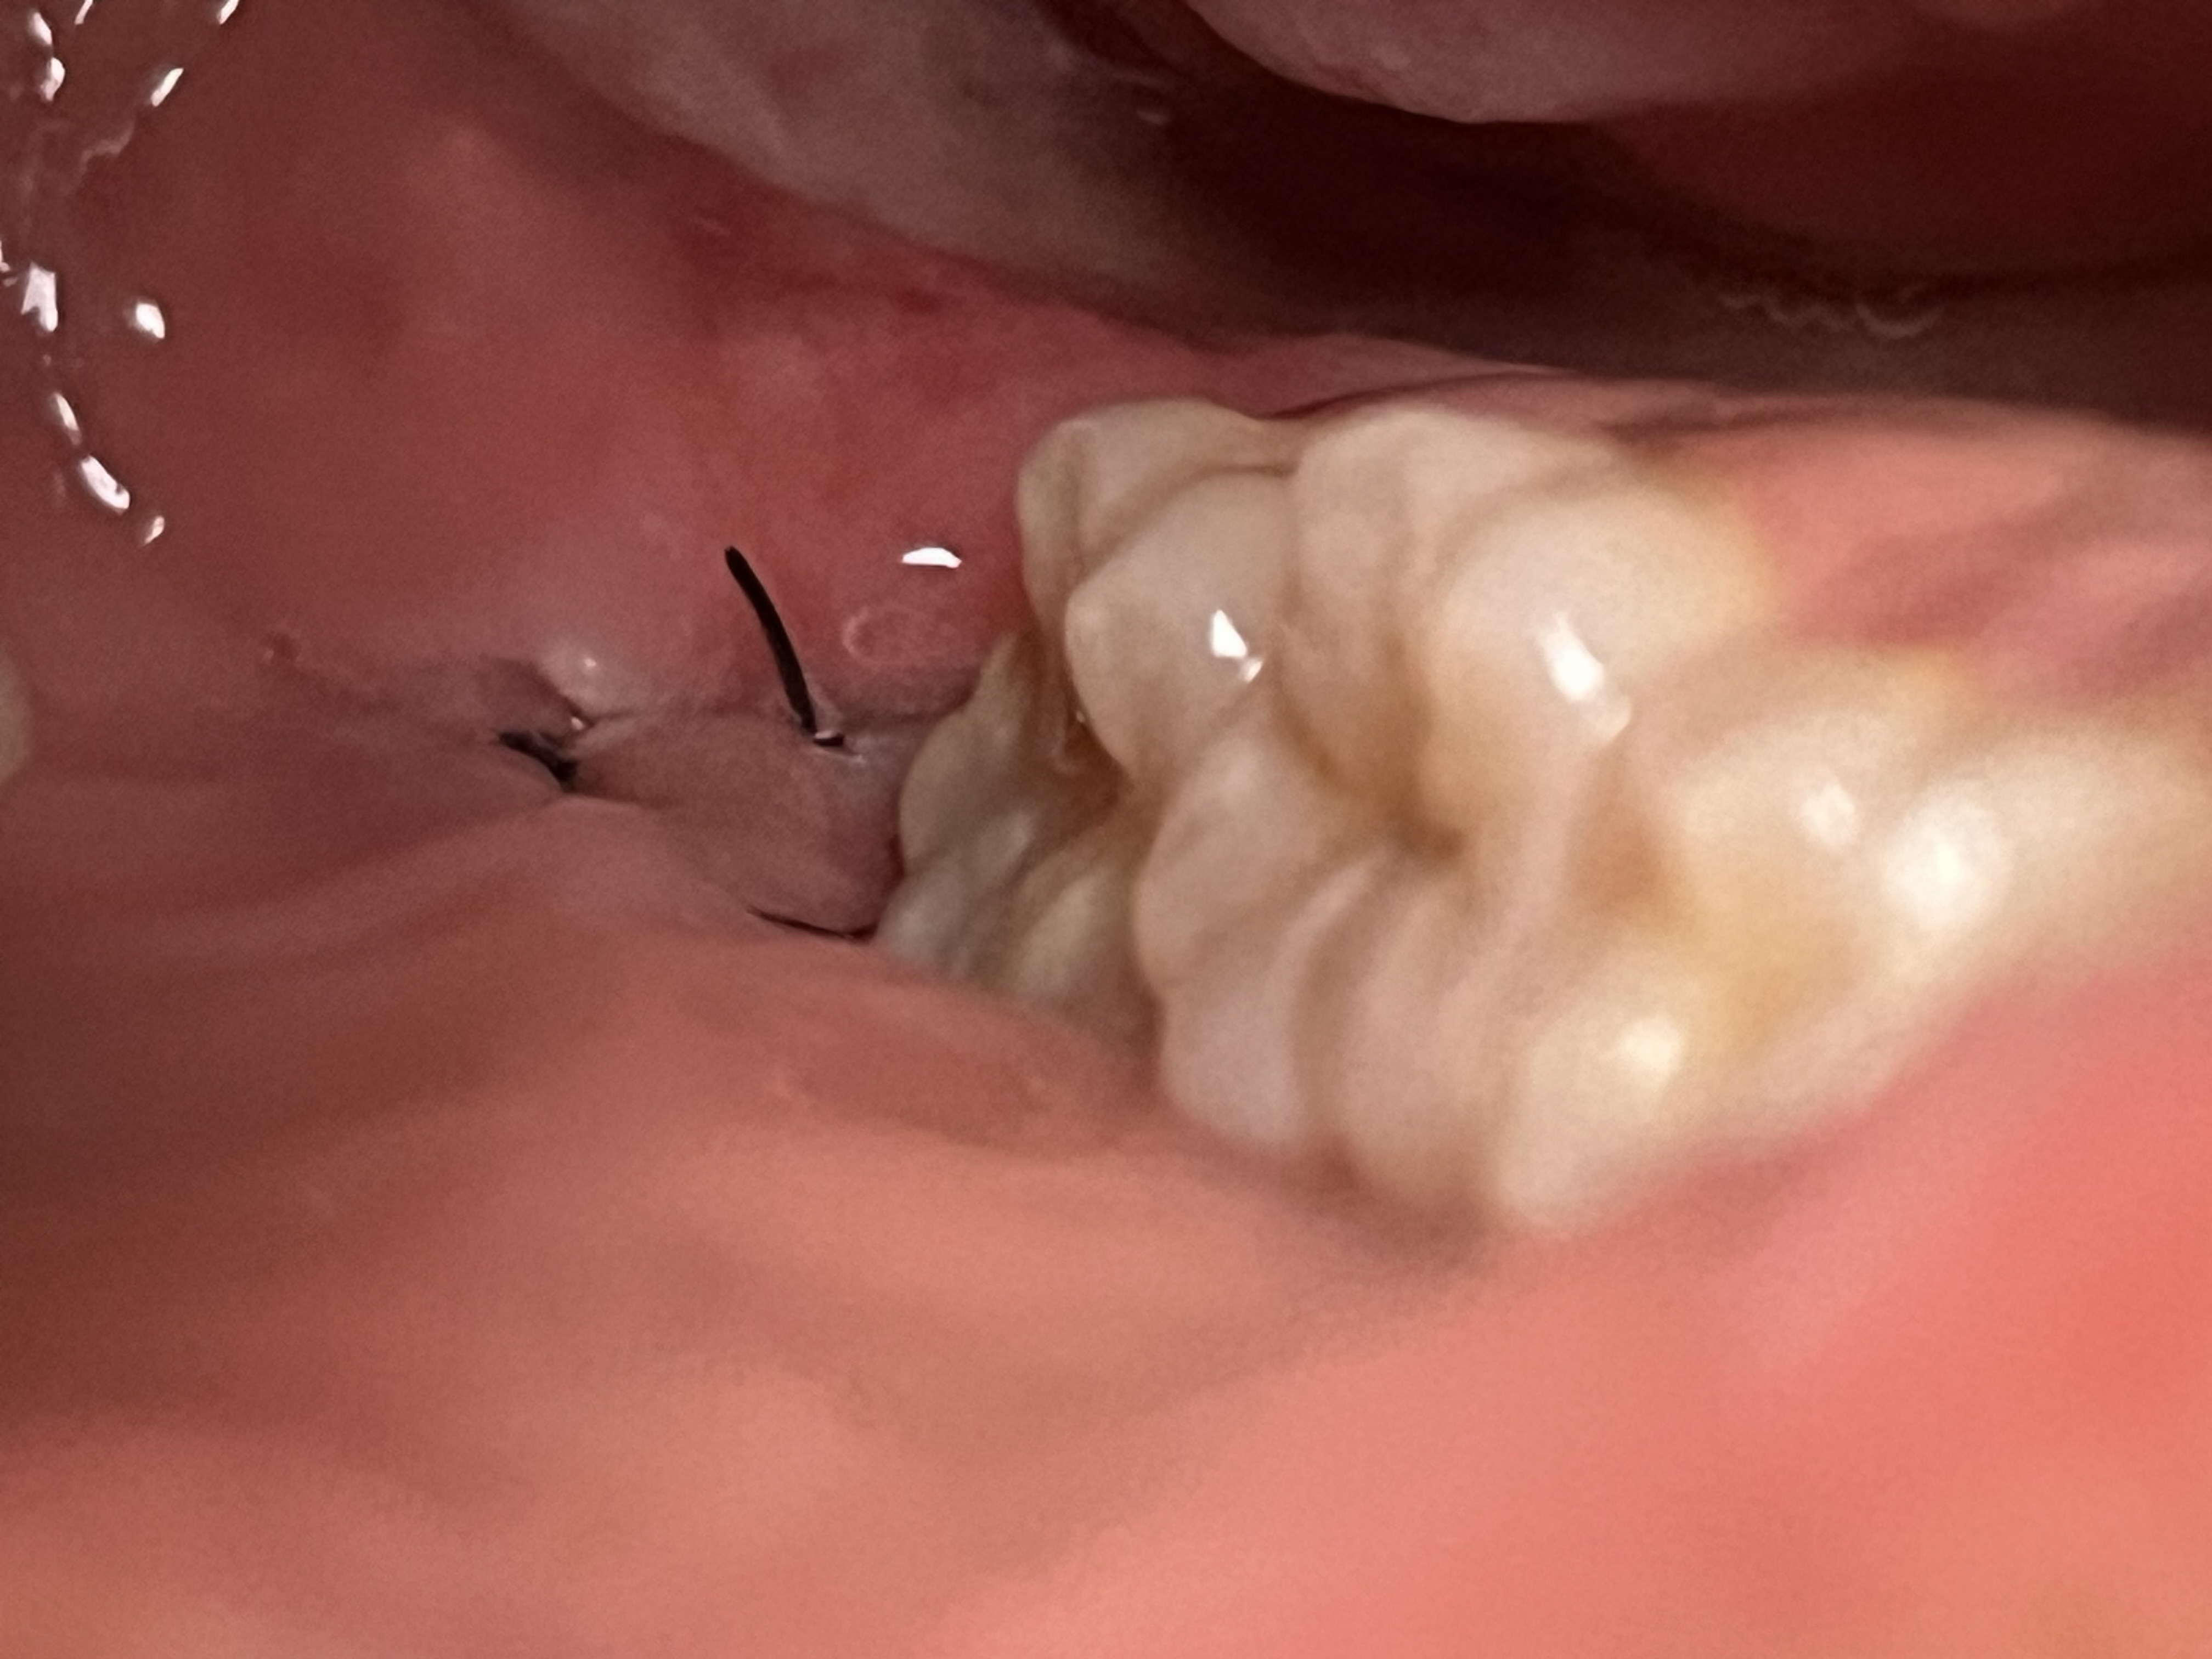

親知らず抜歯後、縫合部分に空いている隙間は埋まりますか?

回答数:2 -